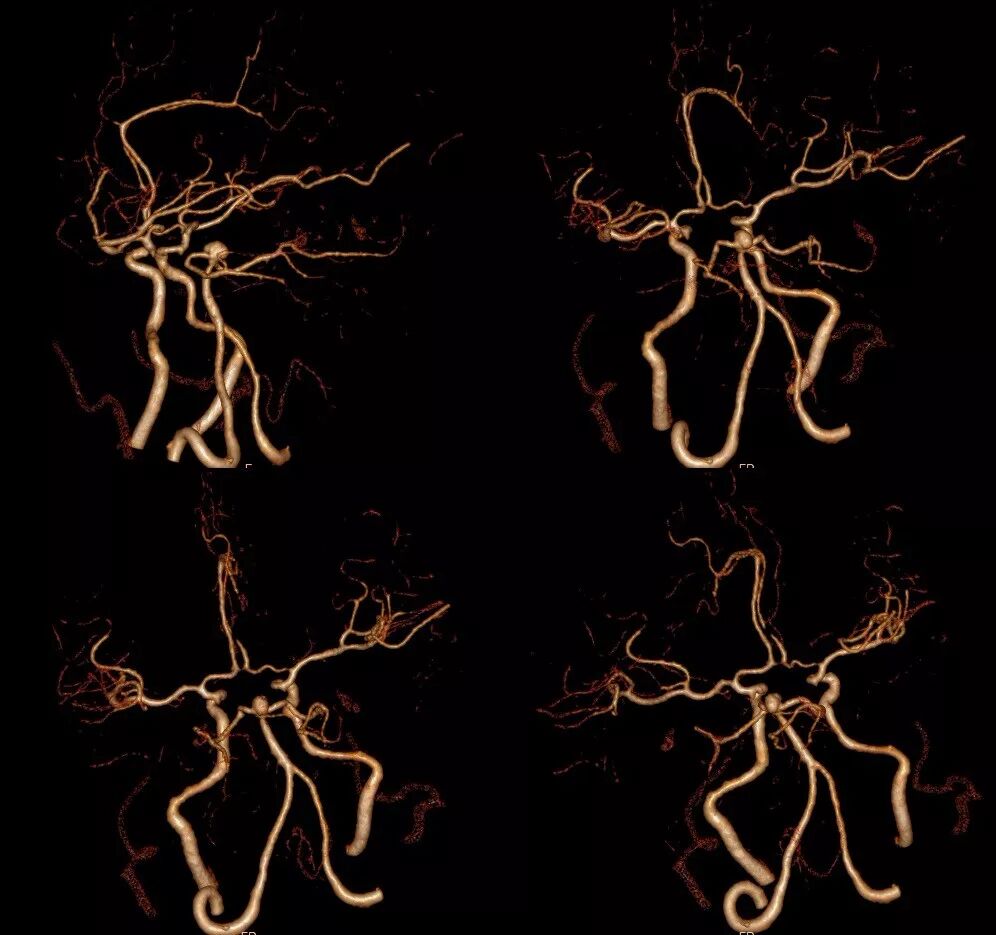

术前CTA:左侧小脑上动脉瘤,瘤体大小2*6mm,余血管无明显异常。(图2-2)

图2-2. 入院头颅CTA提示左侧小脑上动脉瘤,瘤体大小2*6mm。